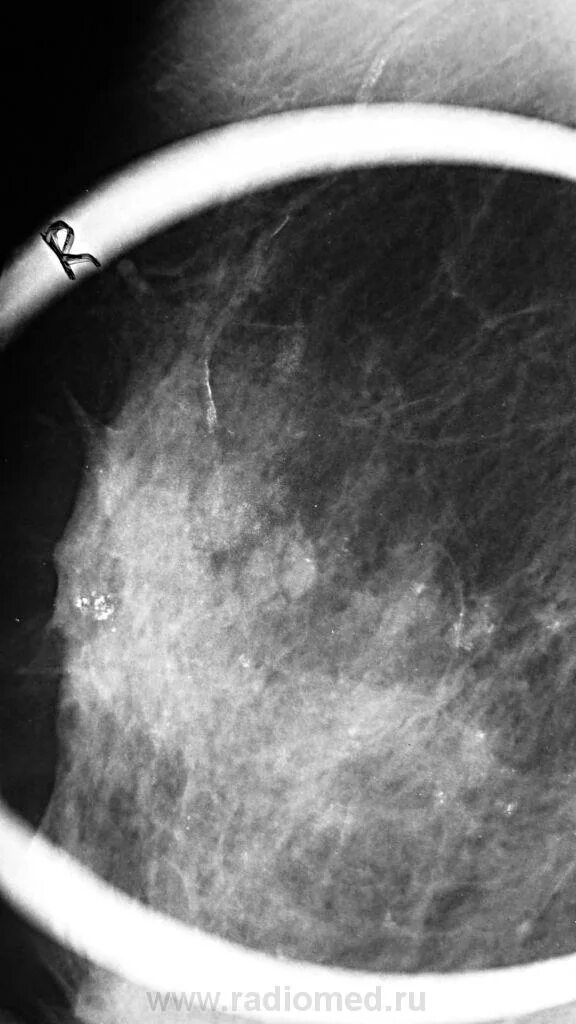

Сгруппированные микрокальцинаты